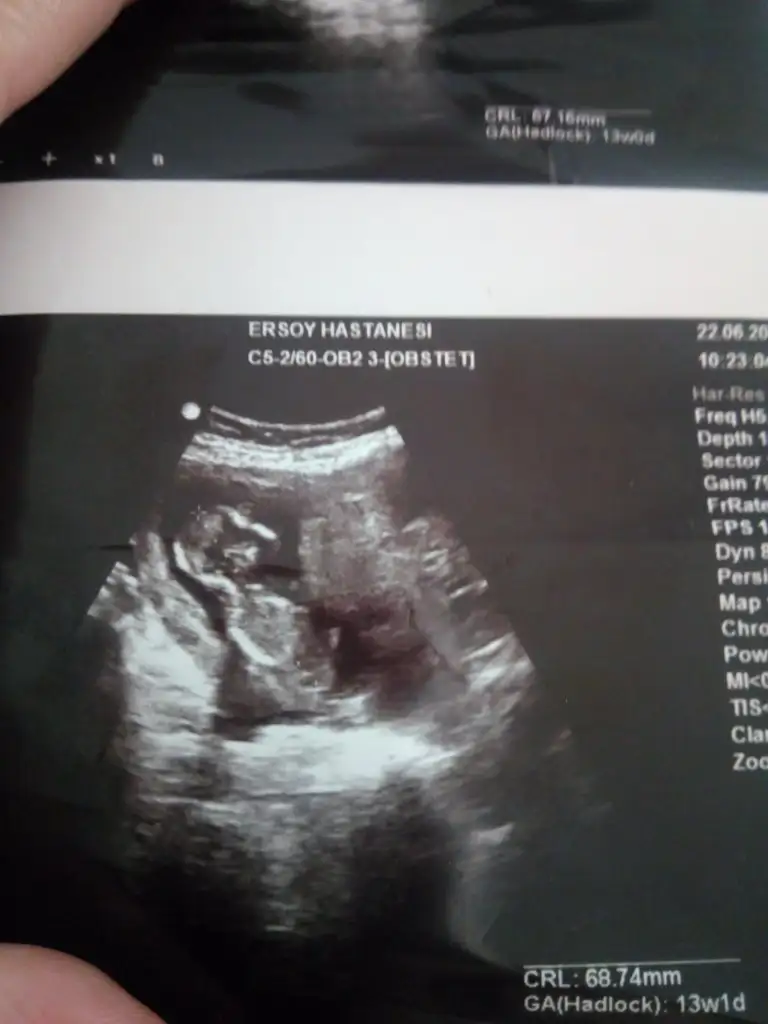

Erkek sankiElimde 13. hafta görüntüleri var 10. Haftada da gitmiştim. 11-12 maalesef yok

O usgde nubu dik görünüyordu şimdiki usg paylaşırmısınız dr daha detaylı bakıyor hayırlısı gönlünüzdeki kızmıBugun doktor yüzde 98 kiz dedi

O usgde nubu dik görünüyordu şimdiki usg paylaşırmısınız dr daha detaylı bakıyor hayırlısı gönlünüzdeki kızmı

Vermedi maalesef ama atıyorum bi umut görürsün diye:) dr tam gorecek oldu döndü goremedik:))Umarım iyi usg verir

Görünmüyor karanlıkta nubuVermedi maalesef ama atıyorum bi umut görürsün diye:) dr tam gorecek oldu döndü goremedik:))